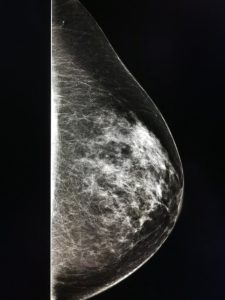

Η πυκνότητα του μαστού μπορεί να προσδιορισθεί με ψηλάφηση, αλλά κυρίως βασίζεται στην αξιολόγηση της σύστασης του μαστού, όπως αυτή απεικονίζεται στη μαστογραφία. Η εικόνα που δίνει ο λιπώδης ιστός στη μαστογραφία είναι πιο διάφανη και σκοτεινή. Αντίθετα ο μαζικός αδένας και ο συνδετικός ιστός εμφανίζονται ως ακτινοσκιερές (πιο φωτεινές) περιοχές.

Υπάρχουν διάφοροι τρόποι ταξινόμησης της πυκνότητας του μαστού. Συνήθως διακρίνονται τέσσερις κατηγορίες:

Κατηγορία 1η : Πολύ χαμηλή πυκνότητα μαστού – Αποτελείται κυρίως από λιπώδη ιστό.

Κατηγορία 2η : Ο μαστός αποτελείται κατά κύριο λόγο από λιπώδη ιστό, ενώ ανευρίσκονται διάσπαρτες περιοχές ινοαδενικών στοιχείων.

Κατηγορία 3η : Ετερογενώς πυκνοί μαστοί, με μεγαλύτερη αναλογία ινοαδενικών στοιχείων σε σχέση με τον λιπώδη ιστό.

Κατηγορία 4η : Ο μαστός αποτελείται σχεδόν εξ’ ολοκλήρου από αδενικό ιστό και χαρακτηρίζεται εξαιρετικά πυκνός.